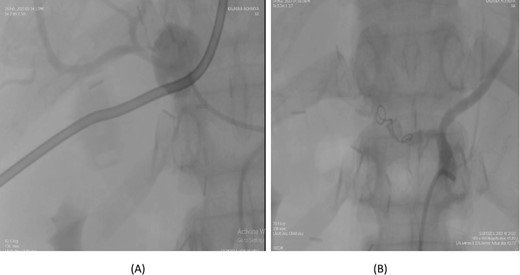

A 56-year-old female underwent a pancreaticoduodenectomy (PD) for pancreatic head adenocarcinoma. On the 6th postoperative day, she presented with nausea and vomiting. A contrast-enhanced CT scan revealed the presence of a pseudoaneurysm originating from the common hepatic artery. Angioembolization was promptly performed to control the bleeding. The procedure was successful, and the patient recovered well postoperatively. At follow-up, the patient was doing fine with no further complications (Fig. 2).

Case 2. (A) CT angiogram showing pseudoaneurysm CHA. (B) Angioembolization of CHA with gel foam